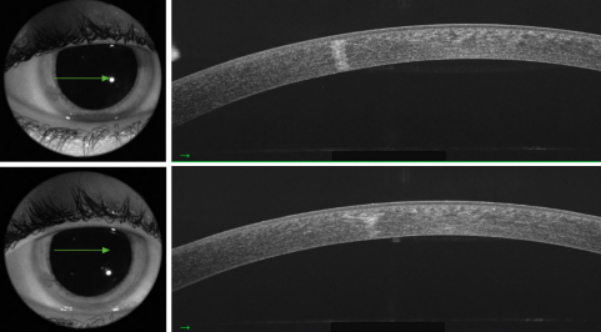

图2. 角膜光学相干断层扫描(OCT)显示,第21天混浊的角膜基质。角膜上皮已经愈合,角膜内皮未受影响。

图1. 最初表现为3处角膜基质浸润和水肿